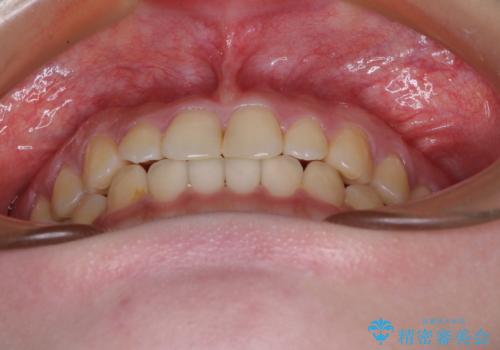

治療途中の奥歯と矯正治療の後戻り インビザライン・ライトによる矯正治療

- 20代女性

- インビザライン・ライト

- 根管治療を行ったままの奥歯と、矯正治療の後戻りを気にして来院された患者様です。

根管治療された歯に症状はなく、オールセラミッククラウンにて補綴治療を行うこととしました。

矯正治療の後戻りは軽微であったため、インビザラインの簡易パッケージであるインビザライン・ライトを用いて歯列を整えることとしました。

クラウンはよりよい咬み合わせで装着したいため、インビザラインを1セット使用して概ね歯列を整えた時点で補綴治療を行い、その後仕上げの矯正治療を行いました。